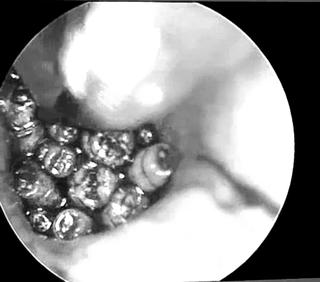

Hàng chục con giòi lấp đầy hòm nhĩ của một bệnh nhân Các bác sĩ tại Bệnh viện Đa khoa tỉnh Quảng Trị vừa phát hiện, gắp hàng chục con giòi sống ra khỏi tai giữa của một bệnh nhân. Hàng chục con giòi lấp đầy hòm nhĩ của một bệnh nhân